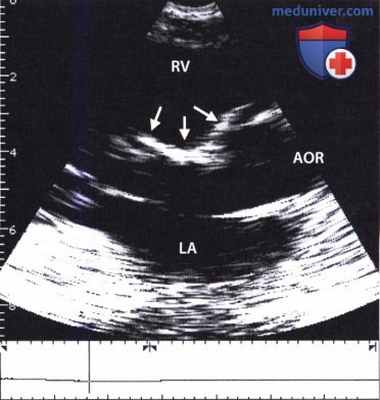

Видео. Закрытие дефекта межжелудочковой перегородки с помощью заплаты у больного с тетрадой Фалло. См. также рисунок ниже. Эхокардиограмма больного с тетрадой Фалло после хирургической коррекции. С помощью заплаты (три стрелки) дефект межжелудочковой перегородки был закрыт и корень аорты (AOR), расположенный «верхом» над дефектом, смещен к левому желудочку (LV); правый желудочек расширен.